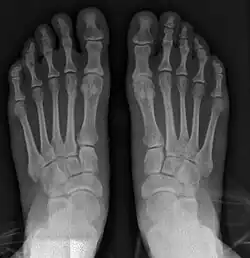

Fig. 8a. Painful hallux valgus and metatarsus primus varus deformity recurrence of left foot after osteotomy surgery

1. For recurrence correction after osteotomy procedure (Fig. 8)

Late deformity recurrence can happen after osteotomy (bone-breaking) procedures because osteotomy surgeries do not specifically stabilize first metatarsal bone.